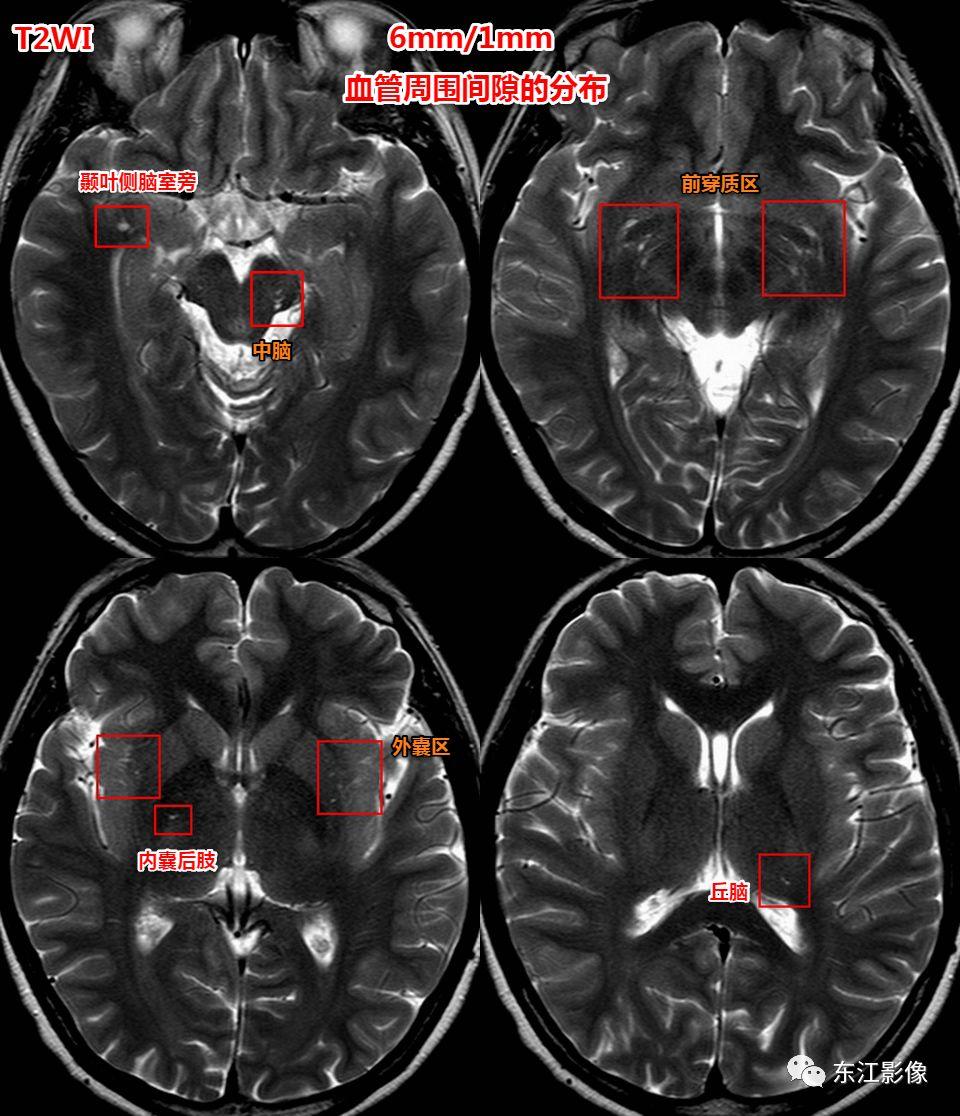

部位

- 常见部位:前穿质区,外囊区,额顶叶皮层下,中脑。——务必熟记!

- 其他部位:丘脑,颞枕叶皮层下,侧脑室周围白质,小脑。

血管周围间隙常见分布。